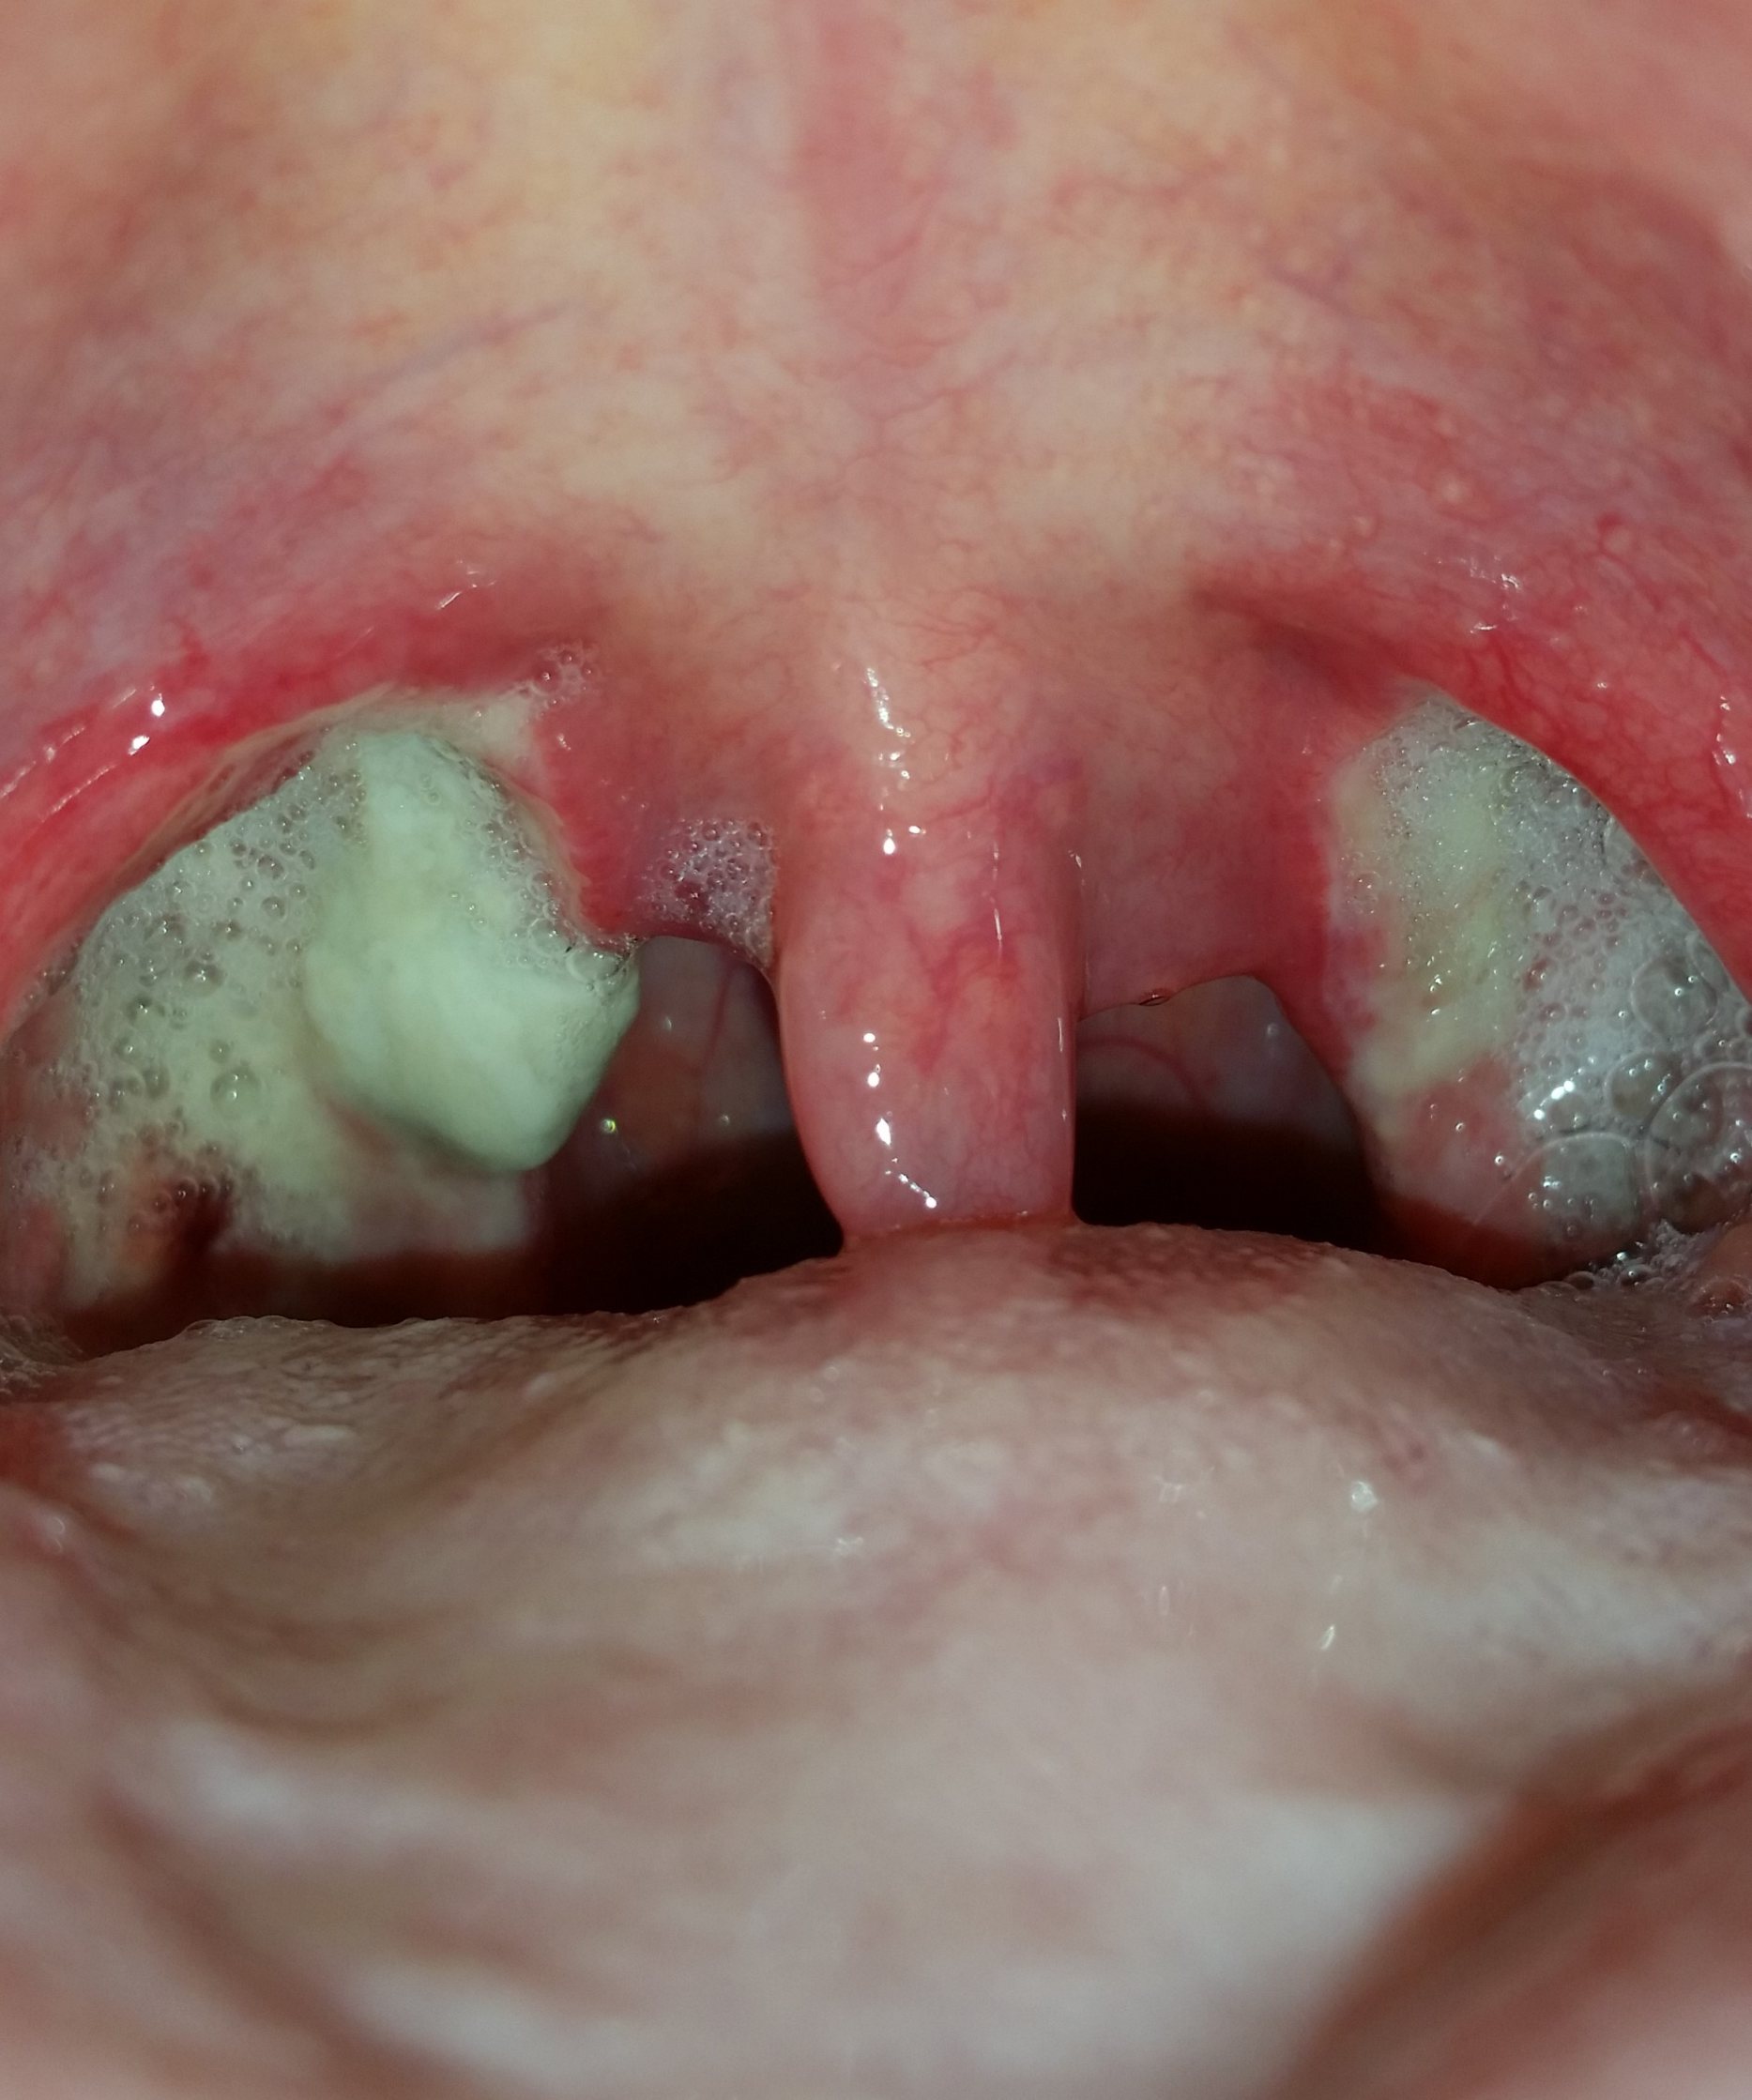

Mandel OP – Bilder Dokumentation Heilungsprozess

- Mandeloperation Tag 9

- Mandeloperation Tag 10

Nach der Operation bildeten sich direkt die weiß, grünlichen Beläge (Fibrinbeläge).

Bis sich die Beläge lösten hatte ich einen leicht „fauligen Mundgeruch“.

Ab dem Tag 9 lösten sich langsam die Beläge. (Ein ziemlich brennendes Gefühl)

Ich werde jetzt erstmal noch mindestens weitere zwei Tage im Krankenhaus bleiben und bin mittlerweile ziemlich durch mit den Nerven. Ich habe große Angst, daß das ganze in den nächsten Tagen wieder passieren könnte. Schmerzen habe ich mittlerweile jedoch fast gar keine mehr. Meine Belege sehen am 7.Tag ungefär so aus wie oben in Bild 13.